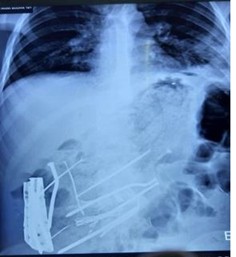

Blood investigations showed total white blood cell counts of 17,300 mm3 with 90% neutrophils. Hemoglobin level was 9.1 g/dL, serum urea, creatinine, and electrolyte levels were normal. Erect chest radiograph showed multiple radiopaque foreign bodies in the epigastrium and right upper quadrant, a grossly dilated stomach, and both domes of the diaphragm showed free gas under the diaphragm (Figure 1).

Figure 1: Radiograph showing multiple metal bezoars